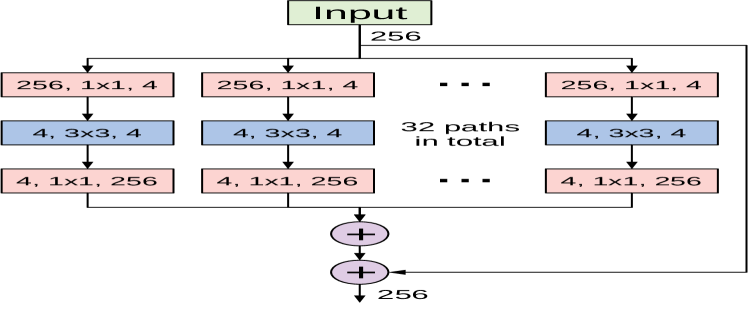

The ResNeXt architecture proposed in [41] is a deep CNN model constructed by stacking residual building blocks of identical topology in a highly modularized fashion. Its simple design shares similarities with the ResNet architecture. ResNeXt also exploits the split-transform-merge strategy of the Inception module in an easy and extendable manner. The ResNeXt building block uses an identical set of transformations in every branch and hence allows the number of branches to be investigated as an independent hyperparameter. ResNeXt refers to the size of the set of transformations as the cardinality, which represents an important dimension for improving the network’s representational power. Figure 4 depicts a ResNeXt building block with a cardinality of 32. Each branch applies the same set of transformations and their outputs are aggregated by summation.